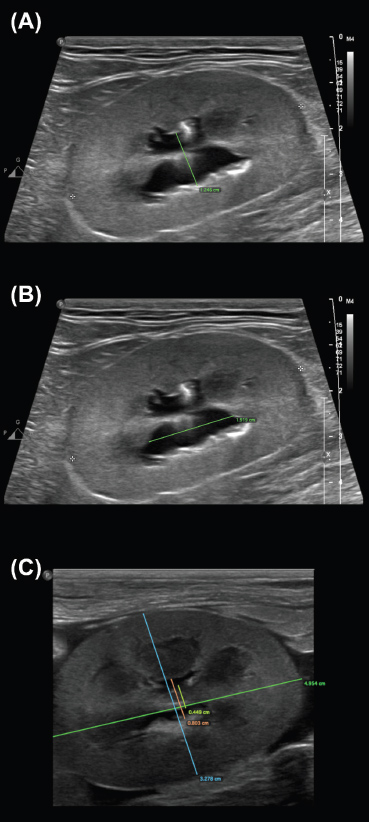

Overall, measurements from the sagittal plane performed worse than those from the dorsal and transverse planes, possibly due to the variable appearance of the renal pelvis in this plane; its margins may undulate, and it might be bisected by the renal crest depending on the level of insonation (Fig. 3). A study of murine kidneys proposed a hydronephrosis grading method that might mitigate the effects of this variation by calculating the percentage of renal height comprised of renal parenchyma (as opposed to renal pelvis) in the sagittal plane (Carpenter et al., 2012). Disappointingly, the interobserver variability of this method was found to be only ‘Moderate’ when applied to cats in our study (Fig. 4).

Fig. 3. Sagittal plane images of multiple kidneys, demonstrating the variable appearance of the renal pelvis. (A, C) The renal pelvis is not bisected by the renal crest. (B, E) The renal pelvis is completely bisected by the renal crest, which varies in thickness and margination between the images. (D) The renal crest incompletely bisects the renal pelvis, appearing as an amorphous echogenic structure in the center of the renal pelvis. Note the undulating margins of the distended renal pelvises in (C) and (D)

Fig. 4. Examples of the “SPP” measurement, adapted from methods proposed in murine kidneys by Carpenter et al., (2012). The longitudinal renal length is measured as a guideline (i). Perpendicular to this, the transverse renal width (ii), renal pelvis diameter (iii), and renal papilla width (iv) are measured, and the percentage of the renal height that is comprised of renal parenchyma (as opposed to pelvis) is calculated. Note that the renal papilla is not visible in (b), which would result in a lower overall percentage of renal parenchyma contributing to renal height in this image.